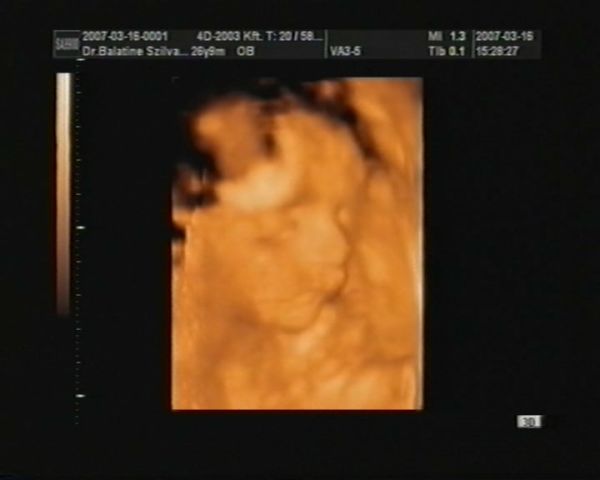

na, a képek, majd még hozok jobbat is, ha el tudom menteni a DVD-ről:

Kép Kistesó

Kép Szabi a 4D-s képen

megvagyunk, minden O.K., KISFIÚ!!!!! :)

De az arca!!!! Petivel összenéztünk, mikor megláttuk: TISZTA SZABOLCS!!!!!!!! :) Olyan édes!